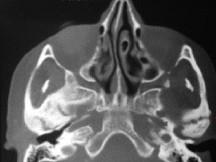

关于颞下颌关节强直(如图)的描述哪项是正确的 ( )

关于颞下颌关节强直(如图)的描述哪项是正确的 ( )![]()

A颞下颌关节外强直是关节外纤维黏连

B颞下颌关节内强直是关节内骨性黏连

C混合性下关节强直是指关节内,外强直同时发生,又称颌间挛缩

D关节及关节周围组织器质性病变造成开口困难或完全不能开口

E颞下颌关节强直常常突然发生